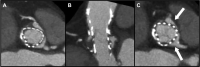

Early Transcatheter Heart Valve Pannus Leading to Coronary Obstruction Managed With Orthotopic Chimney Stenting